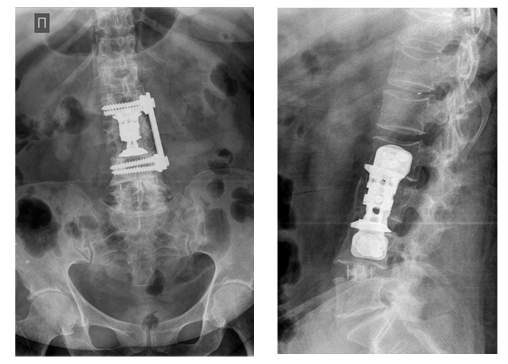

31.03.2016 операция: микрохирургическая декомпрессия корешков спинного мозга на уровне L3, L4-L5, межтеловой спондилодез на уровне L2-L4 имплантом Obelisk и пластиной Vantage, на уровне L4-L5 имплантом Oracle из левостороннего бокового доступа с использованием нейрофизиологического мониторинга.

Рис 5. Послеоперационный рентген-контроль: удаленное тело L 3 позвонка замещено межтеловым имплантатом Obelisc , проведена дополнительная стабилизация вентральной пластиной Vantage , исправлена кифотическая деформация поясничного отдела позвоночника.

04.04.2016 операция: Микрохирургическая декомпрессия корешков спинномозговых нервов на уровне L4-L5 справа. Транскутанная, транспедикулярная фиксация системой Expedium Viper II на уровне L4-L5 с двух сторон.

Рис 6. Послеоперационный рентген-контроль. В межтеловом промежутке L 4-5 находится кейдж Fidji , транспедикулярная система фиксации Expedium Viper 2 на уровне L 4-5.